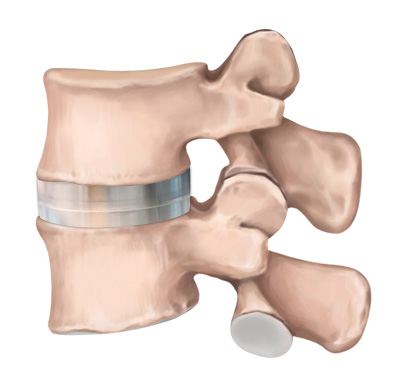

STEP 01

손상된 디스크

STEP 02

손상된 디스크 제거

STEP 03

인공디스크 삽입